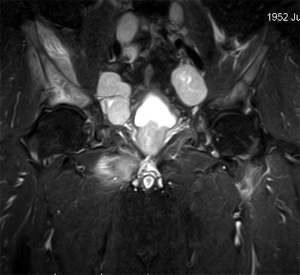

Итак, что же представляет собой МРТ кишечника? Прежде всего, это самый точный неинвазивный метод диагностики, который к тому же не имеет пагубного воздействия на человеческий организм. Данное обследование имеет обширный спектр применения и используется при исследовании заболеваний с подозрением на рак, различных деструктивных, воспалительных и дегенеративных процессов.

С целью повышения диагностических возможностей, при наличии проблем в области кишечника принято использовать контрастные вещества. Они позволяют получить больше сведений и не приводят к возникновению опасности для здоровья пациента. Также при помощи контрастного МРТ возникает возможность отличать поврежденные ткани от воспалительных процессов.